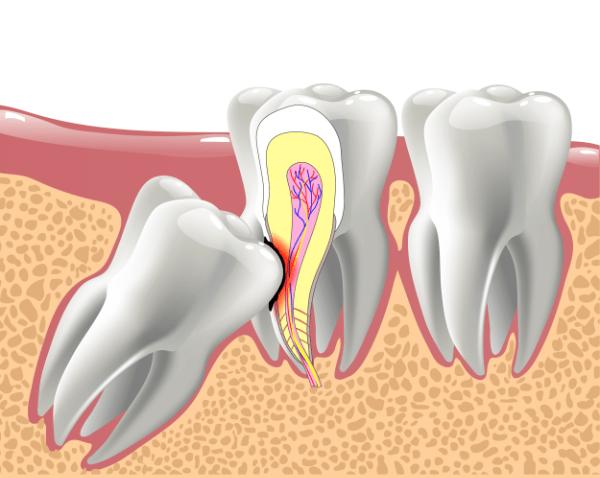

Wenn die Weisheitszähne innerhalb dieser normalen Wachstumsperiode und im Jahr danach ihre normale Position nicht einnehmen, werden sie als eingewachsene Zähne bezeichnet. Dies geschieht häufig aufgrund von Platzmangel im Gebiss oder anderen Einflüssen wie einer kleinen Kieferknochenstruktur oder ungünstigen genetischen Faktoren.

Eingewachsene Weisheitszähne können verschiedene Probleme verursachen, die auf ihre Position und das Fehlen von ausreichendem Platz im Gebiss zurückzuführen sind. Hier sind einige der häufigsten Ursachen und Symptome:

1. Platzmangel: Da die Weisheitszähne die letzten Zähne sind, die im Gebiss wachsen, gibt es oft nicht genügend Platz für sie. Dies kann dazu führen, dass die Zähne einwachsen oder halb aus dem Zahnfleisch herausragen.

Es gibt verschiedene Gründe, warum eine Entfernung der Weisheitszähne notwendig sein kann. Oftmals haben die Weisheitszähne keinen ausreichenden Platz zum Wachsen und bleiben daher eingewachsen oder halb-ausgewachsen im Kiefer zurück. Dies kann zu Schmerzen, Schwellungen, Sensibilität, Behinderungen bei den Mundbewegungen, einem schlechten Mundgeruch und einem unangenehmen Geschmacksempfinden führen.

Das Einwachsen der Zähne kann verschiedene Ursachen haben, wie z.B. Einflüsse auf die normale Entwicklung des Kiefers durch Mundatmung oder frühen Zahnverlust. Auch eine veränderte Ernährungsweise und genetische Veranlagung können dazu führen, dass die Zähne nicht ausreichend Platz haben, um normal zu wachsen.